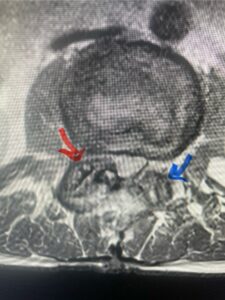

This 61-year-old female with a history of severe osteoporosis and a prior history of a laminectomy from l2-S1 with an L5-S1 instrumented fusion, presents with progressive low back pain and right lower extremity radiculopathy. MRI revealed a grade 1 L2-3 spondylolisthesis with severe stenosis mainly from severe right L2-3 facet joint hypertrophy which was compressing the right L3 descending nerve root. (Fig. 1). She had failed conservative management consisting of physical therapy and pain management with epidurals. She underwent an L1-3 revision laminectomy where we had to dissect a plane underneath the inferior aspect of the L2 lamina. We performed an instrumented fusion at L2-3 with special hydroxyapatite-coated screws to improve fixation to surrounding bone given here severe osteoporosis (Fig. 2) This worked out well and the patient had an uneventful recovery with relief of her leg pain.

Figures 1a: Sagittal and axial T2-weighted lumbar MRIs demonstrating a grade 1 L2-3 spondylolisthesis (red arrow) with severe stenosis secondary to right L2-3 facet hypertrophy (red arrow).

Fig 1b: Note the left L2-3 facet joint (blue arrow) is normal in size compared to the right (red arrow)